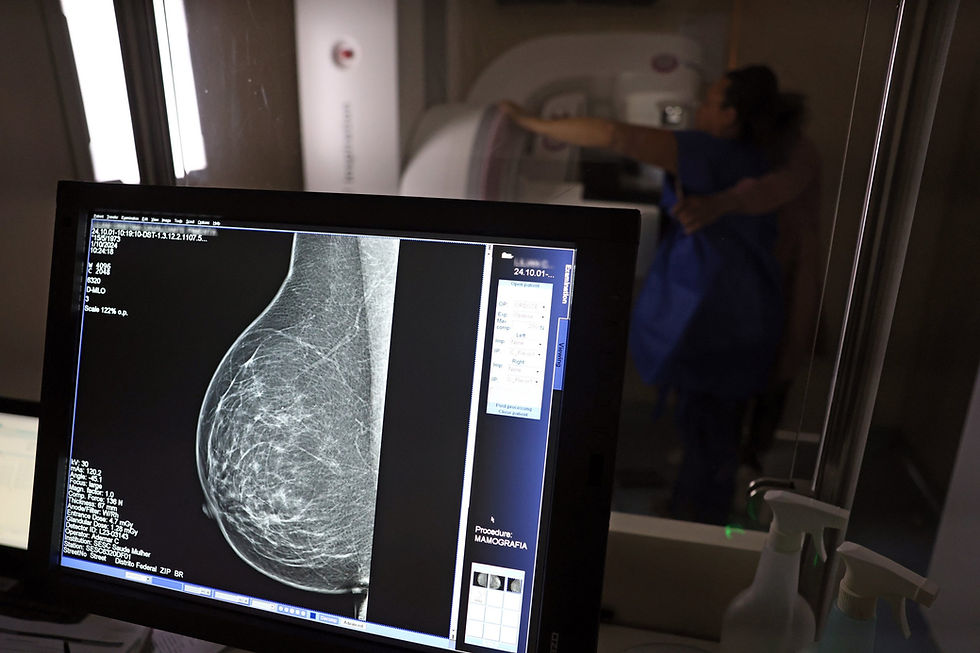

Dados do Panorama do Câncer de Mama revelam que o Brasil possui menos de 24% de cobertura mamográfica, bem abaixo dos 70% recomendados pela Organização Mundial da Saúde (OMS). O estudo também aponta disparidades raciais significativas: 44% das mulheres pretas e pardas recebem diagnóstico tardio, contra 36% das brancas. Especialistas alertam para a necessidade de melhorar o acesso e a conscientização sobre a importância do rastreamento.

Segundo estudos, essas mudanças no estilo de vida podem diminuir em até 30% as chances de desenvolver a doença. Já a prevenção secundária, igualmente crucial, envolve o rastreamento sistemático por meio de mamografias anuais a partir dos 40 anos para a população em geral, com início mais precoce para mulheres que apresentem histórico familiar significativo ou mutações genéticas conhecidas que aumentem o risco. Muitas mulheres enfrentam dificuldades logísticas, como a distância dos serviços de saúde e horários incompatíveis com suas rotinas, o que contribui para baixa adesão, além da falta de conscientização sobre a importância da mamografia.

Ao identificar uma lesão suspeita na mamografia, o próximo passo é realizar uma biópsia para confirmação histológica. Uma vez diagnosticado, o tratamento pode incluir cirurgia (desde abordagens conservadoras até mastectomia), hormonioterapia, quimioterapia, radioterapia ou imunoterapia, dependendo do tipo e estágio do tumor.